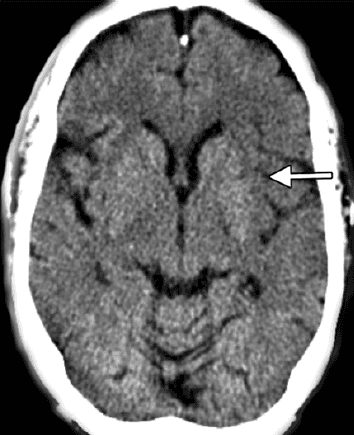

La expansión de la selección por imagen consolida un cambio de paradigma: ya no basta con detectar hipodensidad, oclusión o edema. Hoy se espera que la imagen distinga entre núcleo isquémico establecido, penumbra recuperable y escenarios en los que intervenir puede cambiar el pronóstico funcional del paciente.

El informe radiológico deja de ser una descripción retrospectiva del evento. Ahora define elegibilidad terapéutica, orienta trombólisis o trombectomía en ventanas extendidas, y exige lectura integrada de TAC simple, angioTAC, perfusión y, cuando corresponde, RM multiparamétrica. La interpretación ya no es solo diagnóstica: es estratégica.

En la práctica, esto exige una secuencia operativa clara: TAC sin contraste para descartar hemorragia y detectar signos tempranos, angioTAC para identificar oclusión de gran vaso y estudios de perfusión o RM para valorar tejido recuperable. La calidad del desenlace depende cada vez más de la calidad y velocidad de esa cadena.

La diferencia entre penumbra y núcleo, entre mismatch real y falsa irreversibilidad, o entre un mimic y un infarto verdadero, ya no es una sutileza académica. Es la frontera entre tratar o no tratar. Por eso, la neurorradiología de ACV exige lectura contextual, dominio de pitfalls y protocolos institucionales que soporten decisiones de alto impacto clínico.